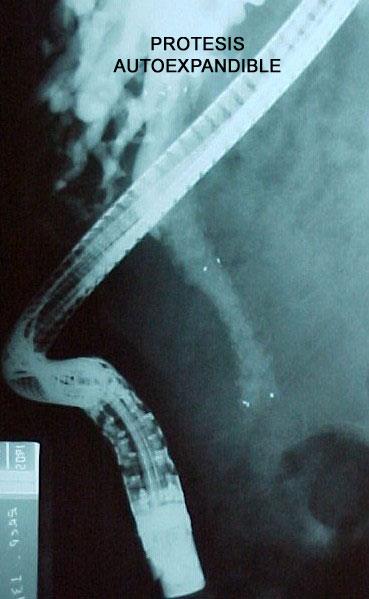

Isquemia mesentérica: Aguda y crónica